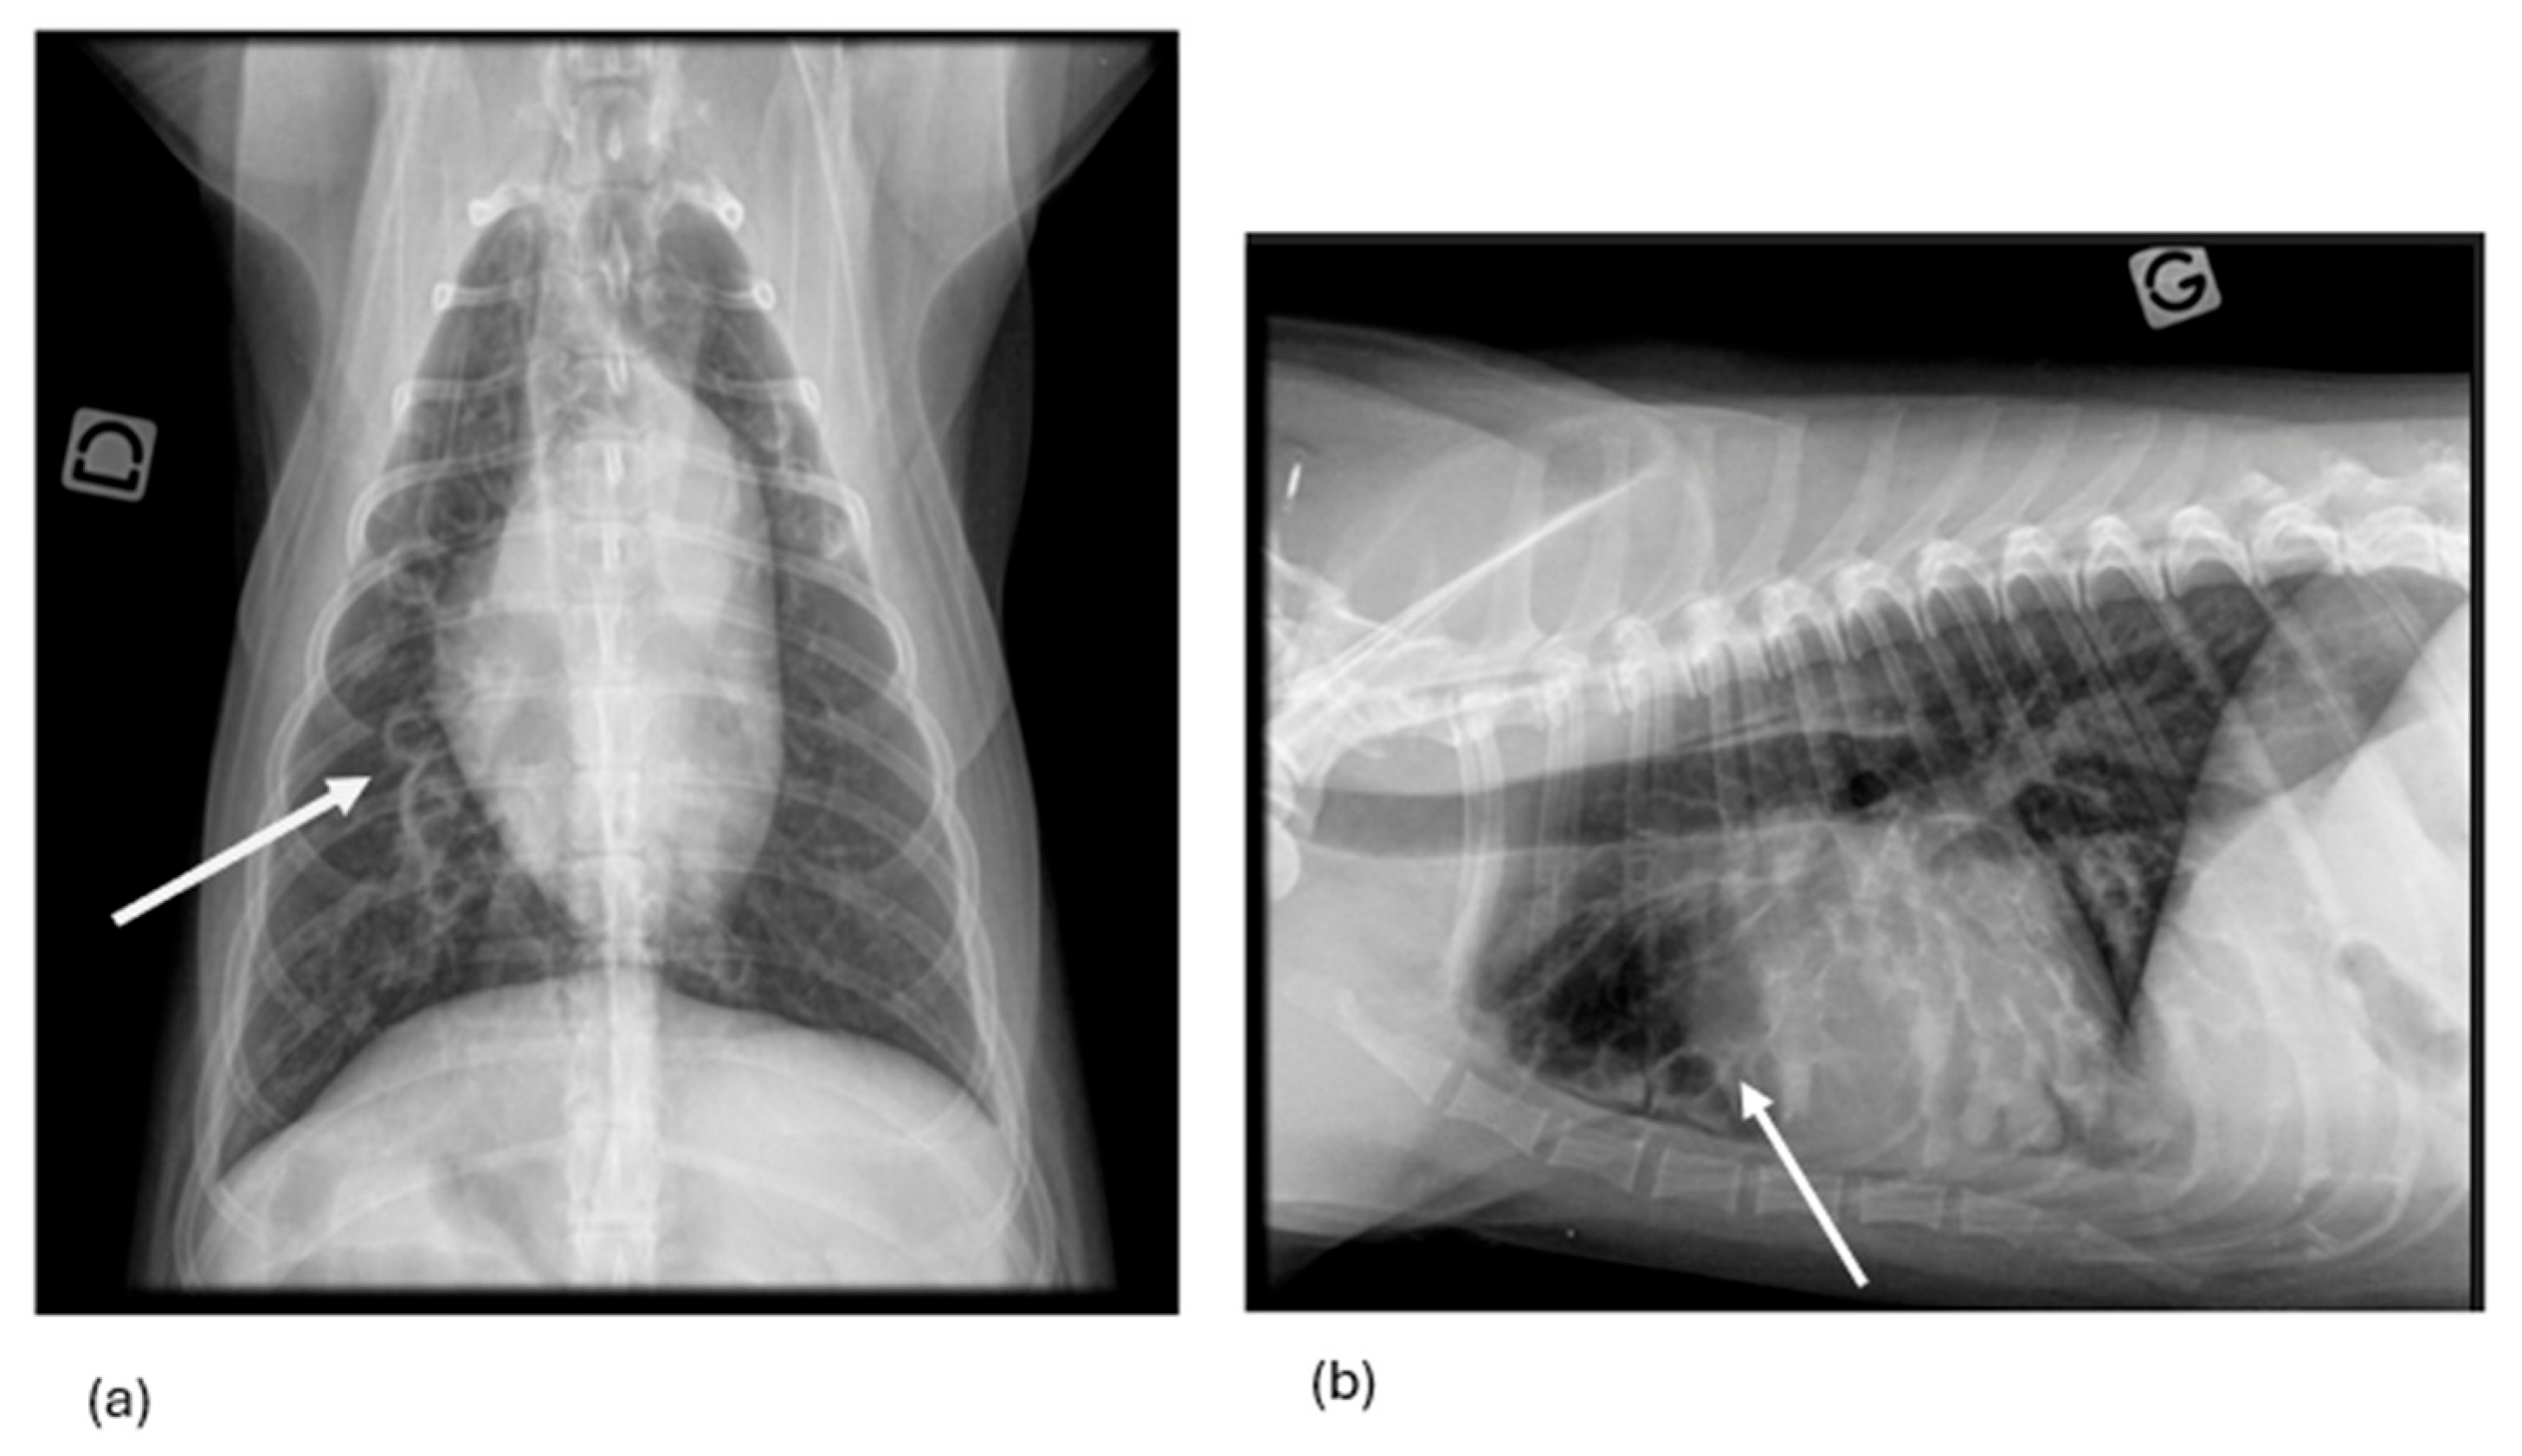

3.1.7. Thoracic Radiography Findings

3.2.1. Thoracic Radiography Versus Endoscopy